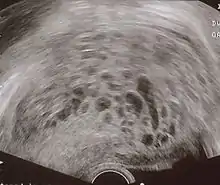

The diagnosis is strongly suggested by ultrasound (sonogram), but definitive diagnosis requires histopathological examination. On ultrasound, the mole resembles a bunch of grapes ("cluster of grapes" or "honeycombed uterus" or "snow-storm").[14] There is increased trophoblast proliferation and enlarging of the chorionic villi, and angiogenesis in the trophoblasts is impaired.[15]

Transvaginal ultrasonography showing a molar pregnancy.